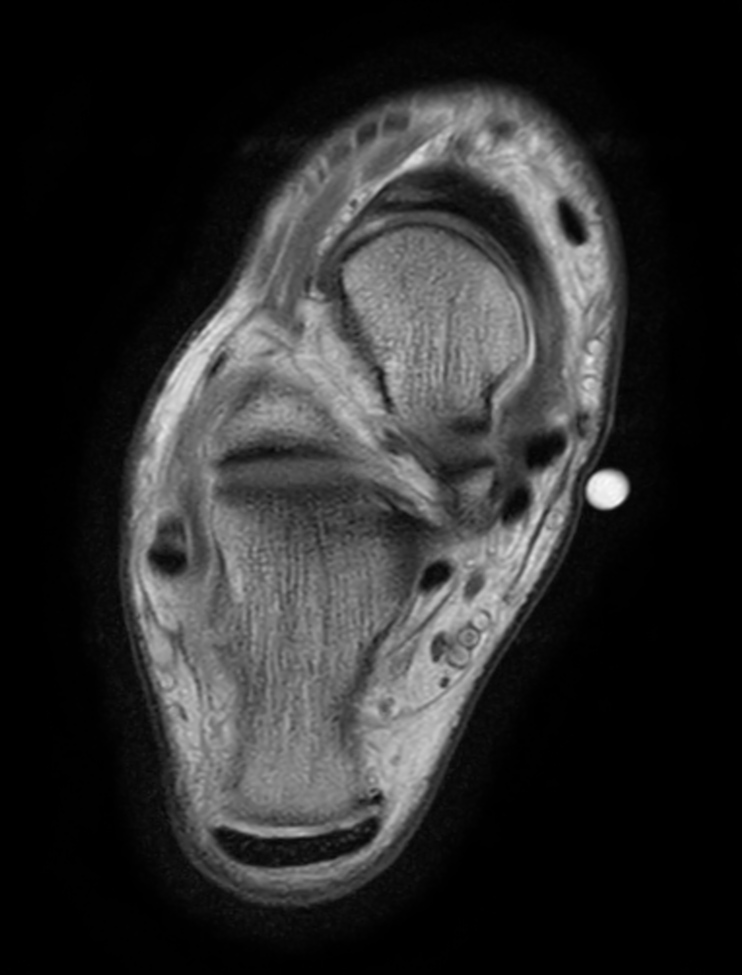

Axial PDw TSE - mDIXON XD (In Phase)